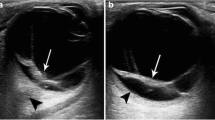

This paper presents a novel method for automated detection of retinal detachment from ocular ultrasound image using digital image processing and computational techniques. Retinal detachment (RD) is an ocular emergency in which retina gets detached from the tissues lying underneath it and often requires immediate intervention to prevent rapid, irreversible vision loss. Direct fundoscopy and visual field testing are most common methods for the detection of RD. These methods are difficult to perform and they do not completely rule out retinal detachment. Generally, Ophthalmologists use ocular ultrasound to enhance their clinical acumen in detecting RD. Sometimes it is difficult to extract diagnostic features from ultrasound (USG) images due to its poor quality. Also, noise present in the image would cause misinterpretation during visual inspection;this demands development of intelligent and automated techniques for detection of retinal detachment. Further, the paper proposes a novel frame work for accurate and automatic retinal detachment using image processing techniques and mathematical analysis of detached area contour detected within the ocular globe. Furthermore, the estimation of diagnostic parameters, indicative of retinal detachment is also computed. Based on the mathematical analysis, three such parameters, percentage area of detached retina (PADR) compared to the ocular globe, angular width of detachment (α) and maximum radial distance of detachment to choroid layer beneath it (β), are calculated. These estimated parameters are very useful in determining the exact location and extent of retinal detachment. Results obtained through the proposed retinal detachment detection scheme are validated by the radiologist.